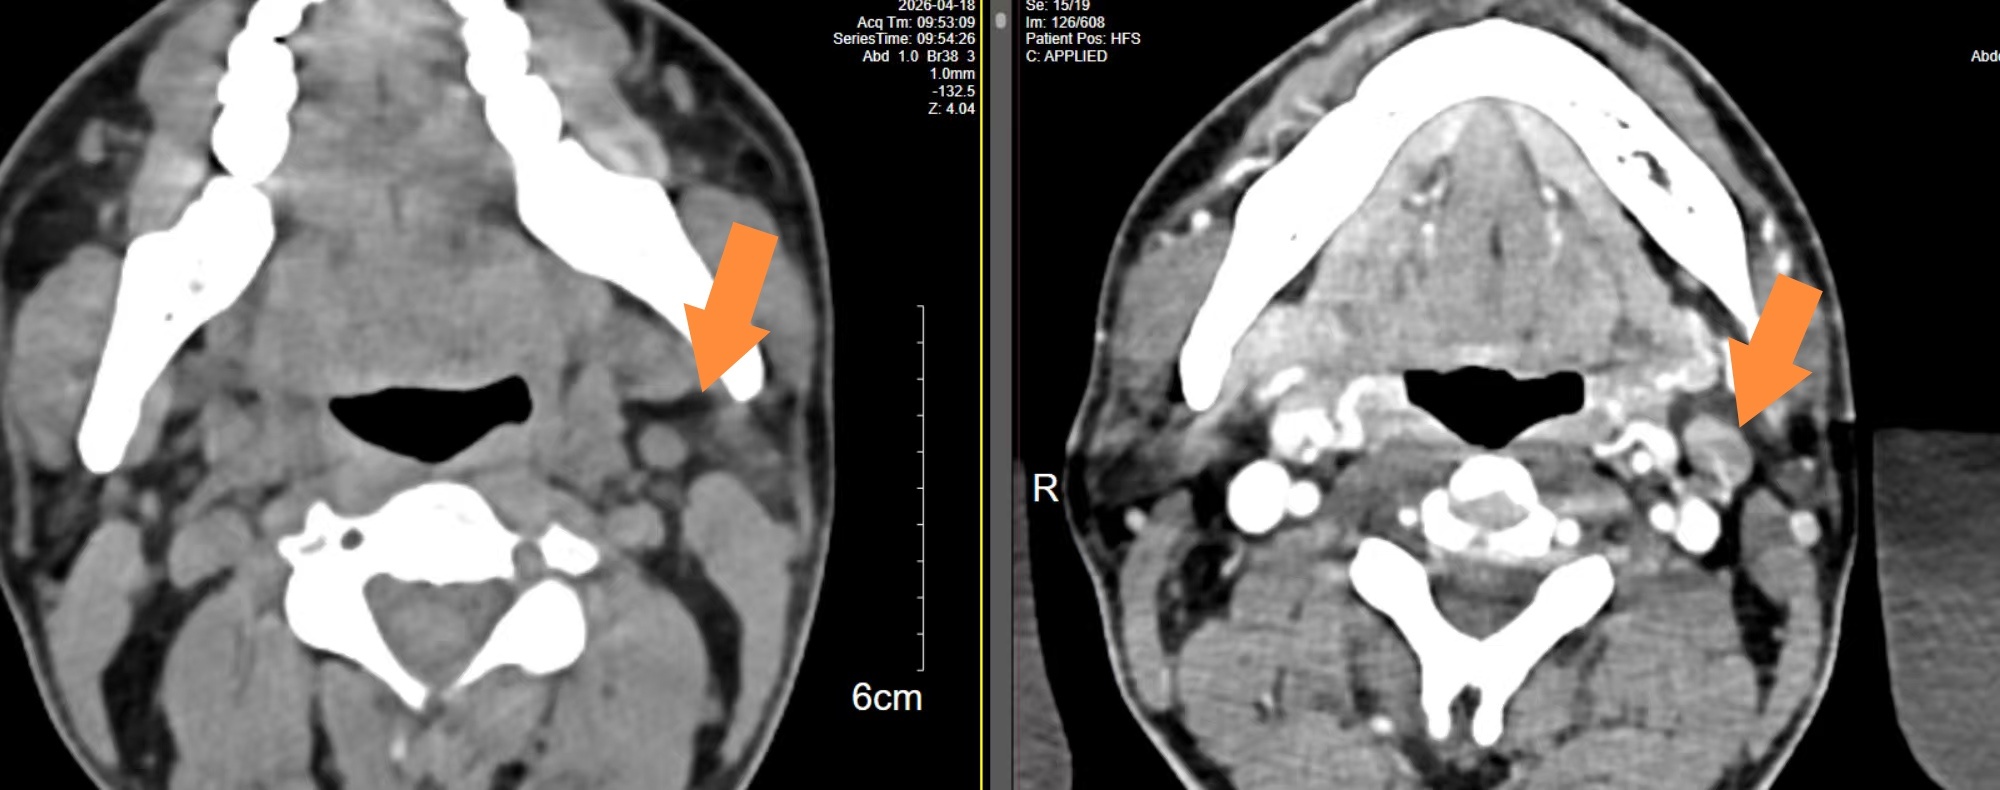

目前2周期化疗后第14天查白细胞低了,中性粒细胞0.6*10*9,打了两次短效升白针(隔天一次),第18天查恢复了,只是睡眠很差,常需要助眠药辅助睡眠,今日今日复查了颈胸腹部CT,大多数病灶都缩小了大概50-70%不等,我还是很欣慰,我是准备4周期后再做PETCT行中期评估。